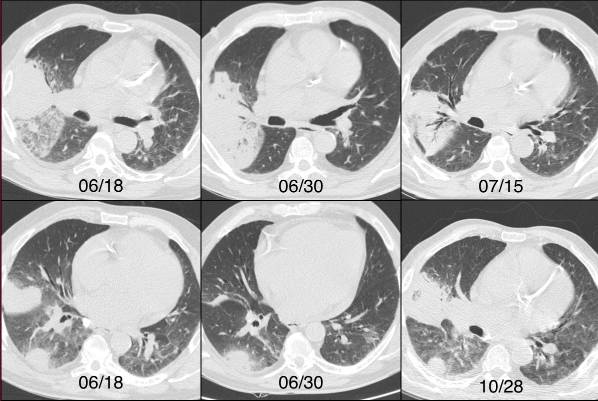

图1 一例酗酒和营养不良患者右肺慢性实变的进展。半侵袭性曲霉病

影像学特征包括肺段实变可能是双侧的。可能表现空洞和胸膜增厚。多发结节可能与实变相关。